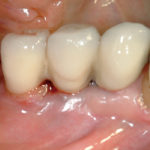

La malattia perimplantare: cause e fattori di rischio

Mucosite-perimplantare-2